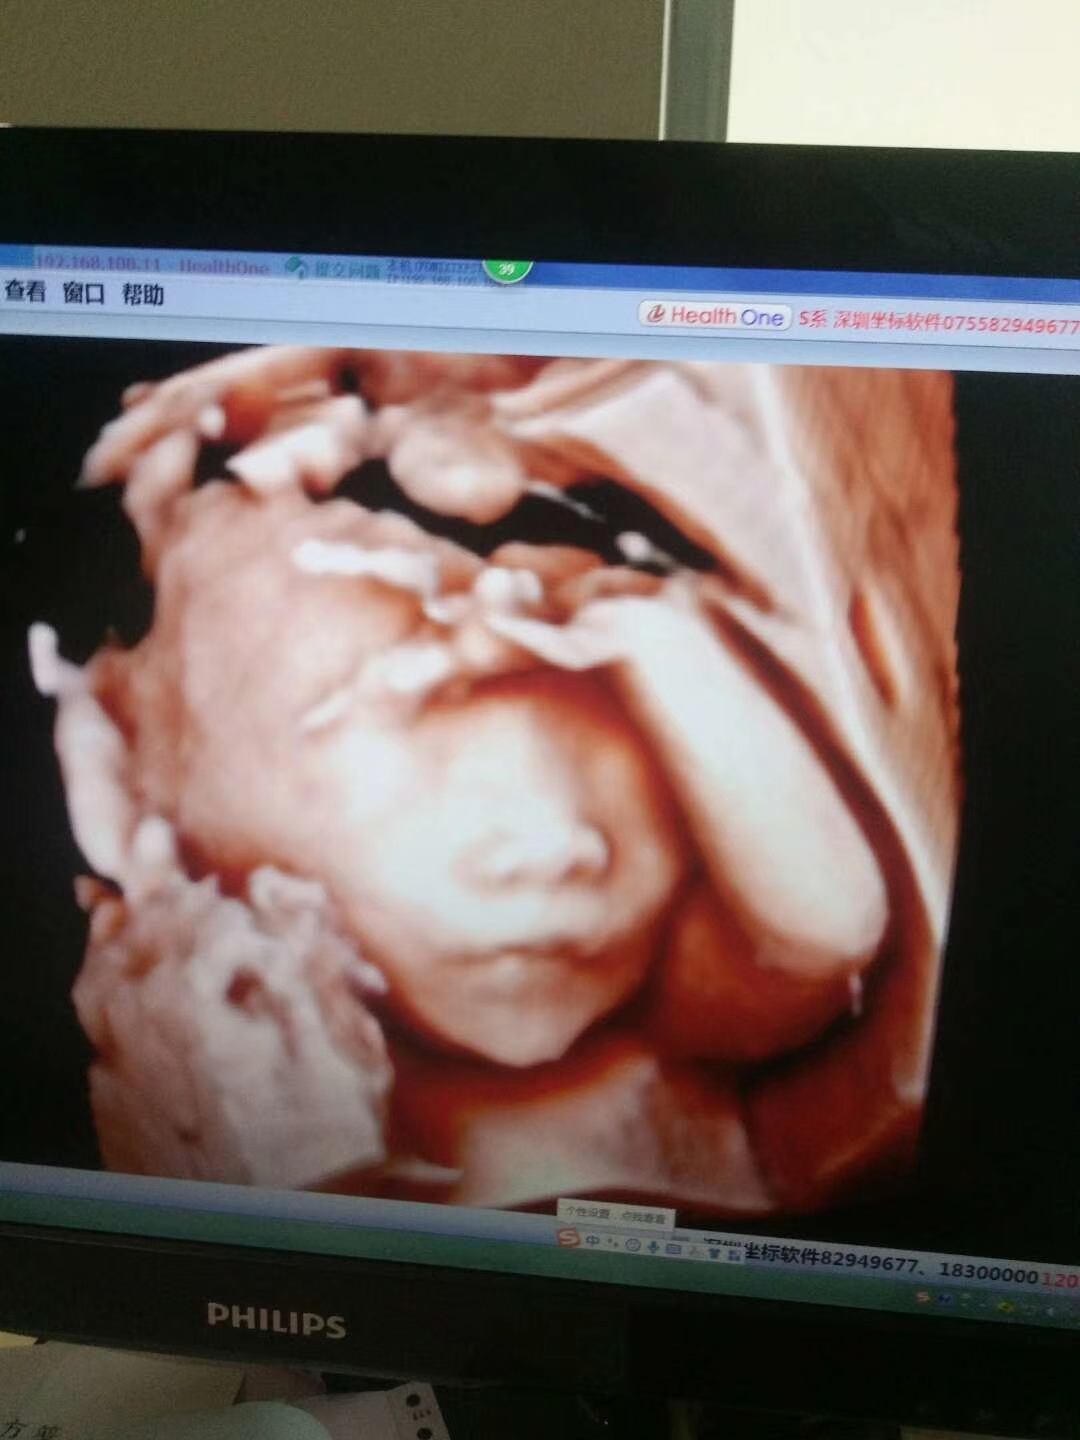

孕33周+2天

好清楚,应该是女宝

看五官像女孩子,尖下巴,很秀气